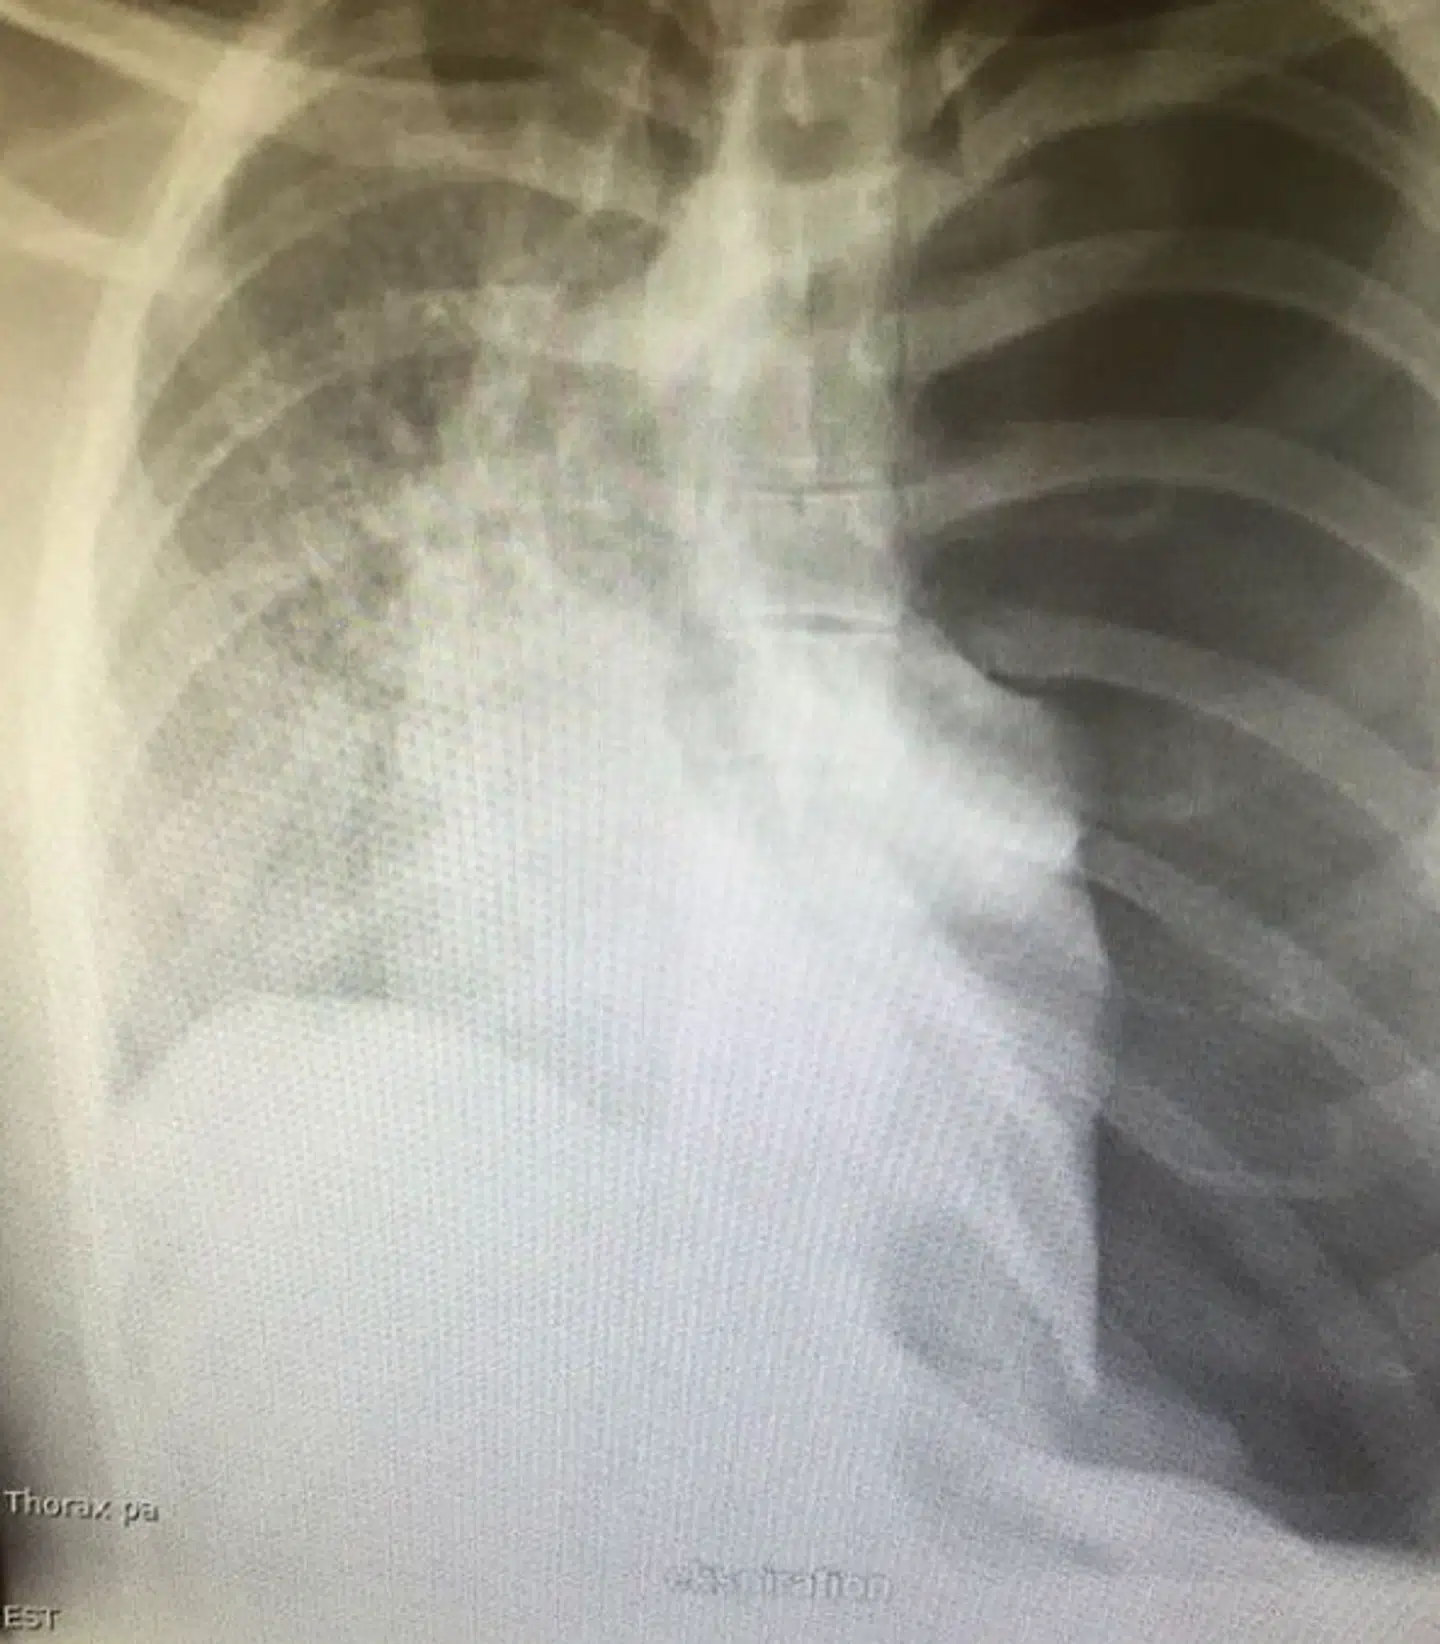

Hvad William ikke vidste, var, at den i virkeligheden var helt gal. Williams lunge var totalkollapset, og hans hjerte samt luftrør havde flyttet sig, fik han at vide.

»Jeg tog til lægen, men blev hurtigt sendt videre til akut røntgen. Jeg havde egentlig ikke ondt og tog selv afsted på sygehuset. Dér blev jeg så sendt i akutmodtagelsen.«

Ifølge lægerne havde der dannet sig nogle små blærer på lungen, som kan have forårsaget kollapset. Trykket fra kollapset gjorde så, at hjerte og luftrør rykkede på sig, hvilket, ifølge lægerne, giver den livsfarlige tilstand, gengiver William.